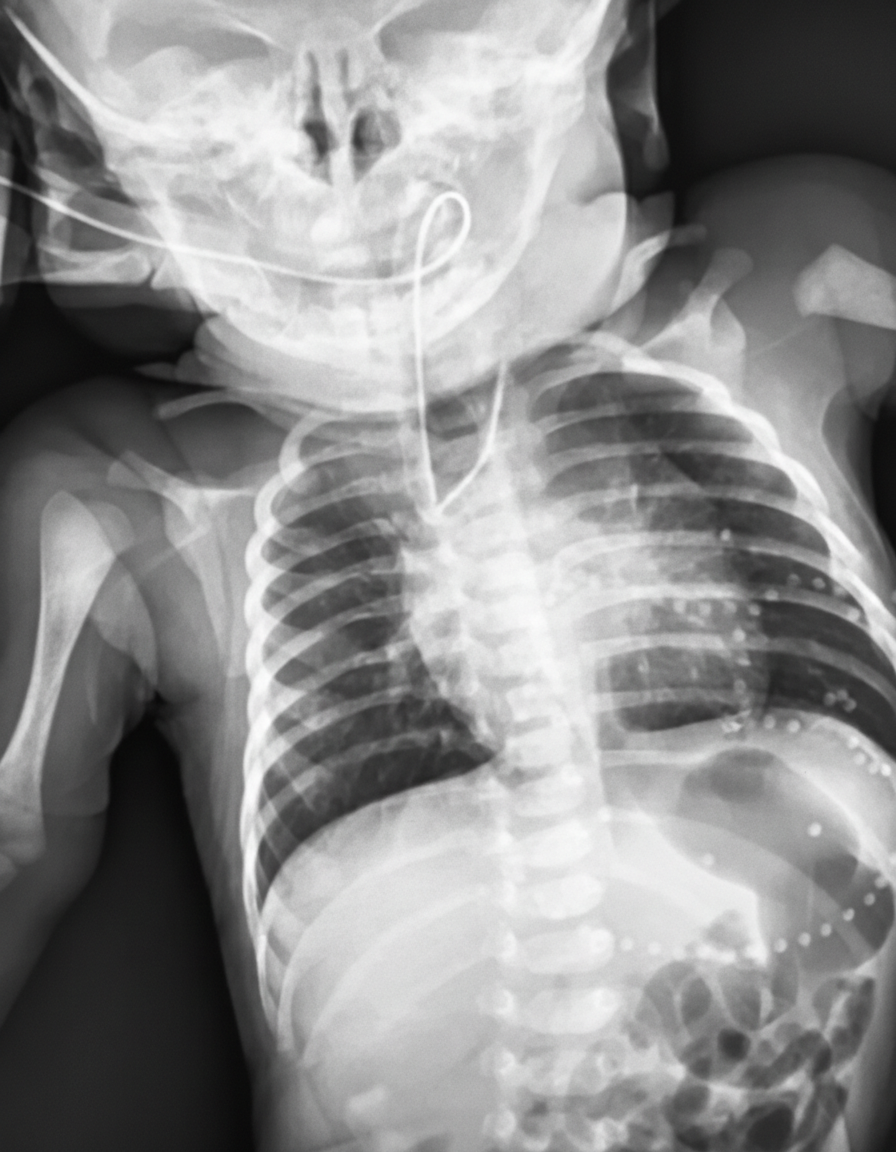

Thirty minutes after delivery, a 3400-g (7.5-lb) female newborn develops cyanosis of her lips and oral mucosa. She was born at 36 weeks of gestation to a 30-year-old woman, gravida 1, para 0. Apgar scores are 7 and 8 at 1 and 5 minutes, respectively. Pregnancy was complicated by polyhydramnios. The patient's temperature is 37°C (98.6°F), pulse is 144/min, respirations are 52/min, and blood pressure is 70/40 mm Hg. Examination shows foaming and drooling at the mouth. Bilateral crackles are heard at the lung bases. There is a harsh 3/6 systolic murmur along the left sternal border. The abdomen is soft and mildly distended. There is an anterior ectopic anus. Insertion of a nasogastric tube is attempted. An x-ray of the chest and abdomen is shown. Which of the following is the most likely diagnosis?